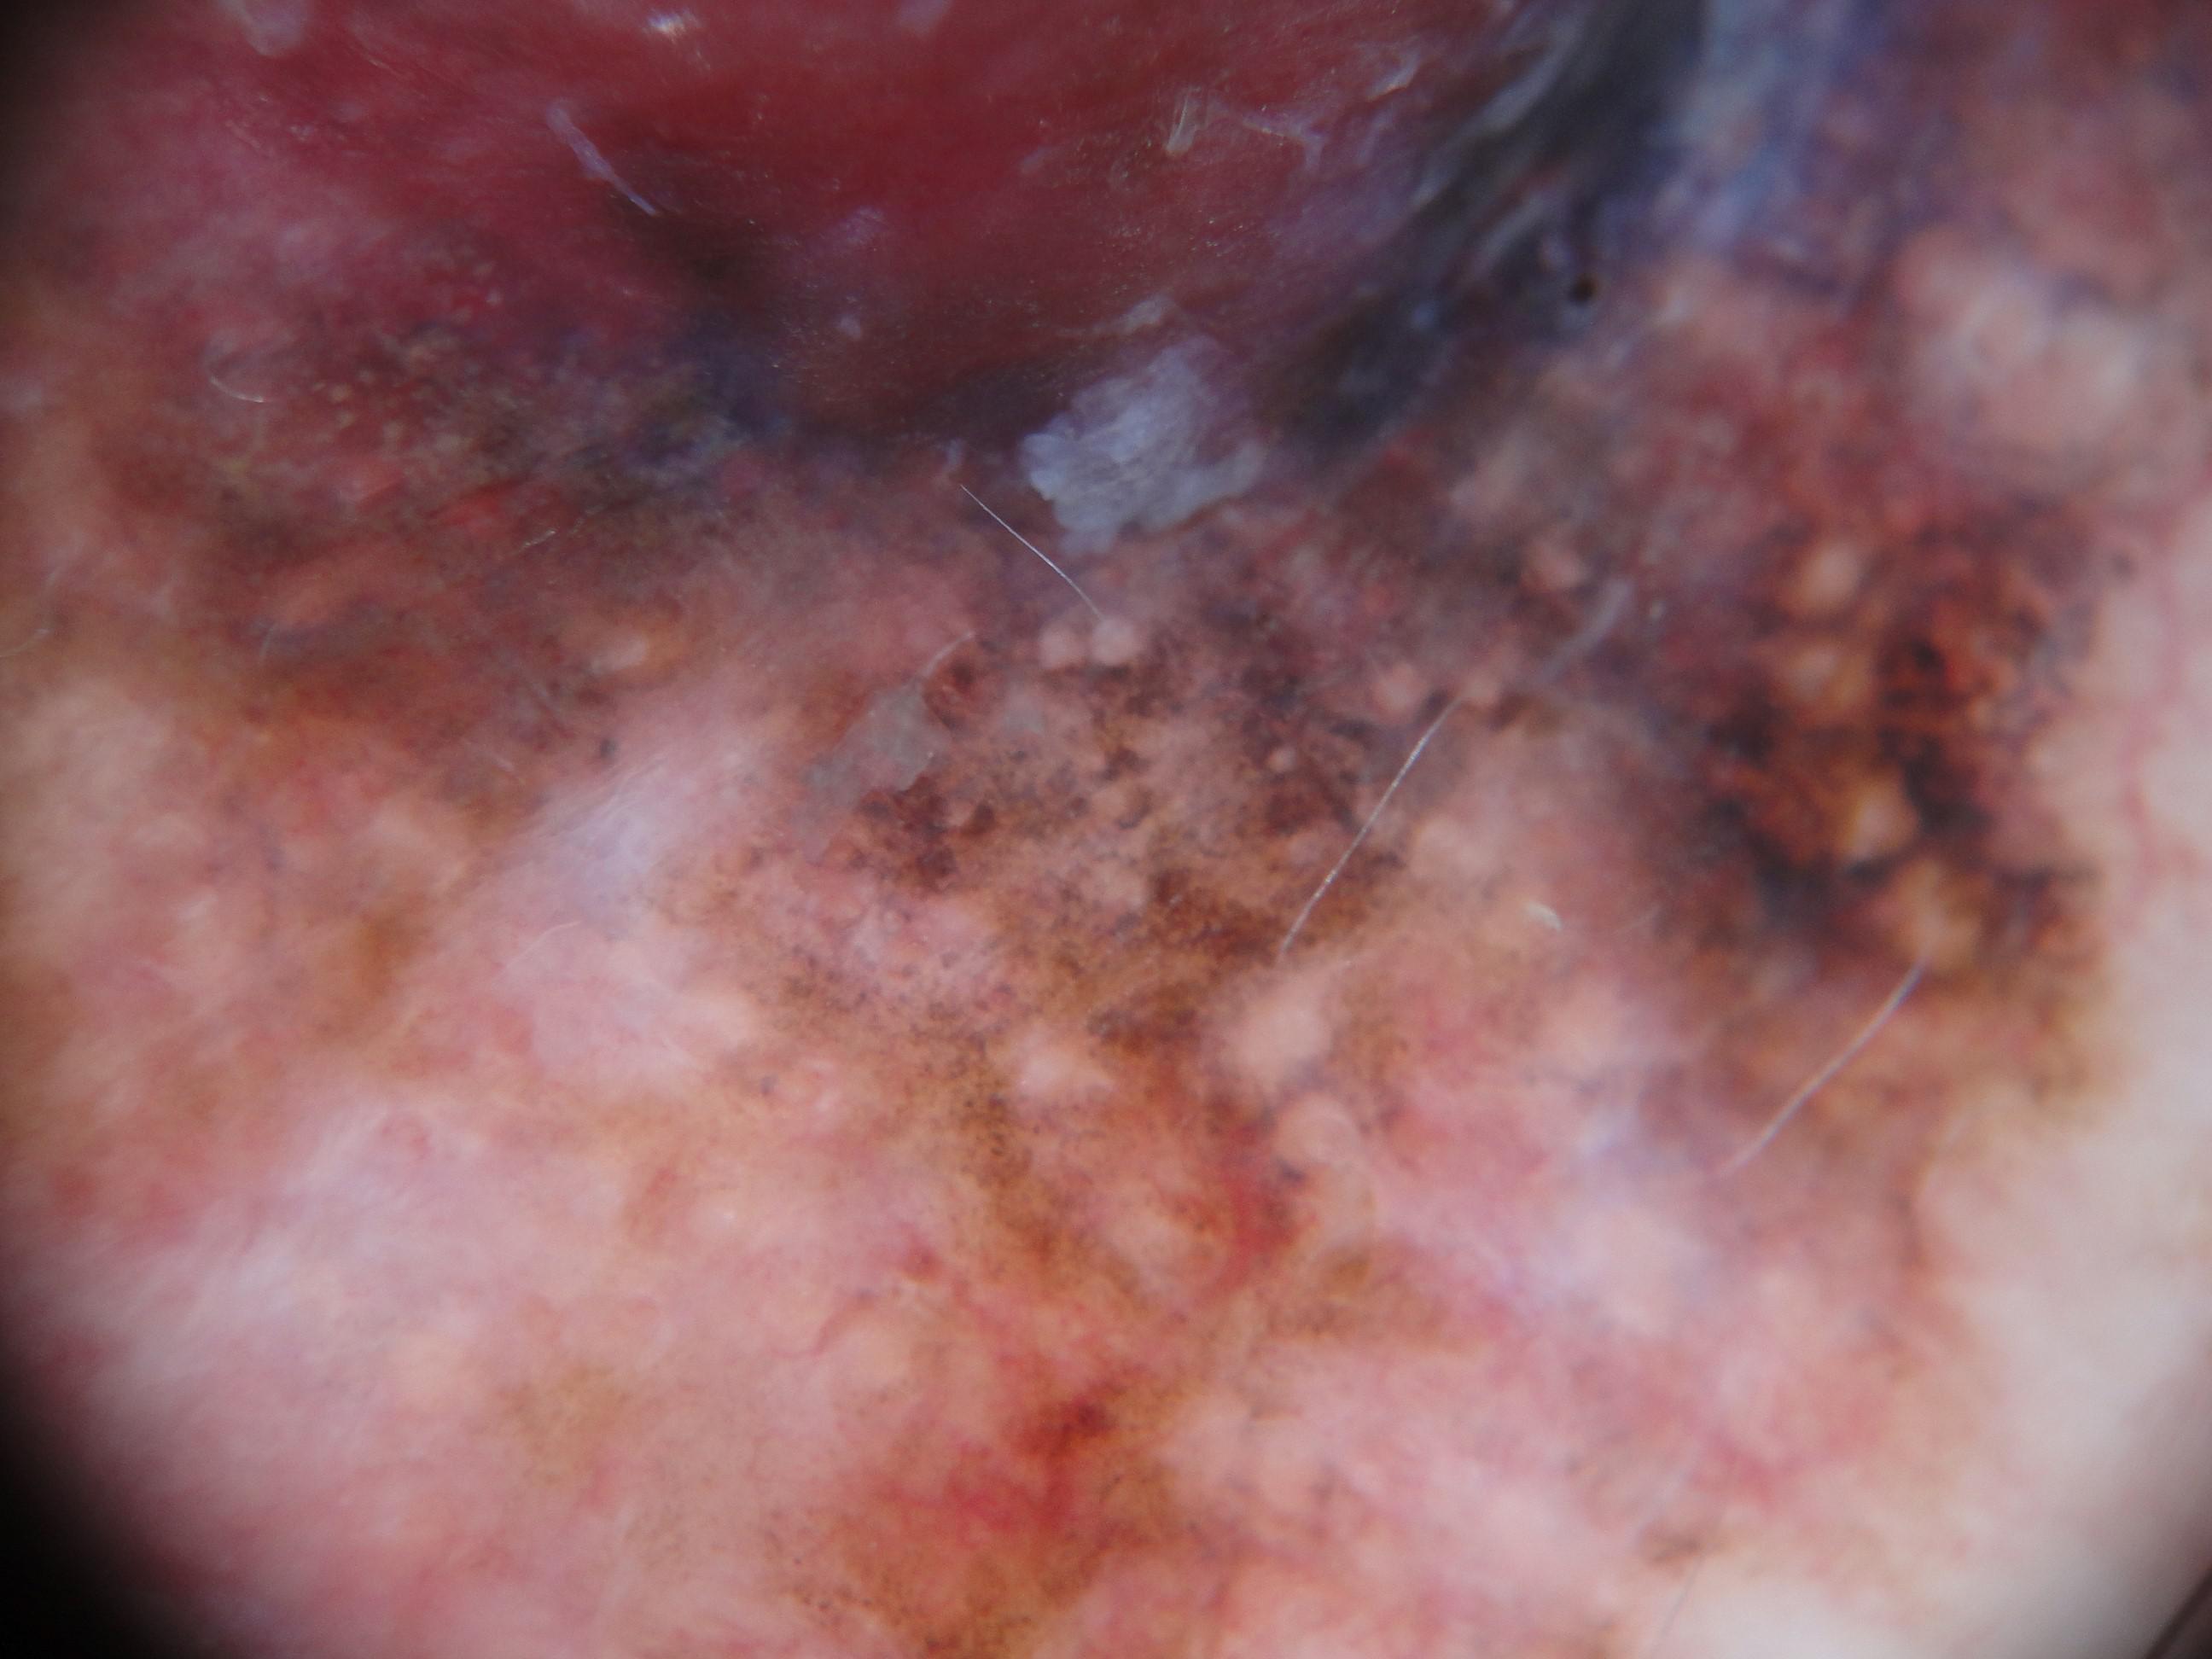

{

"age_approx": 85,

"anatom_site_general": "upper extremity",

"concomitant_biopsy": true,

"dermoscopic_type": "contact non-polarized",

"diagnosis_1": "Malignant",

"diagnosis_2": "Malignant melanocytic proliferations (Melanoma)",

"diagnosis_3": "Melanoma Invasive",

"diagnosis_confirm_type": "histopathology",

"family_hx_mm": false,

"image_type": "dermoscopic",

"mel_thick_mm": "4.30",

"melanocytic": true,

"patient_id": "IP_0126628",

"personal_hx_mm": false,

"sex": "male"

}